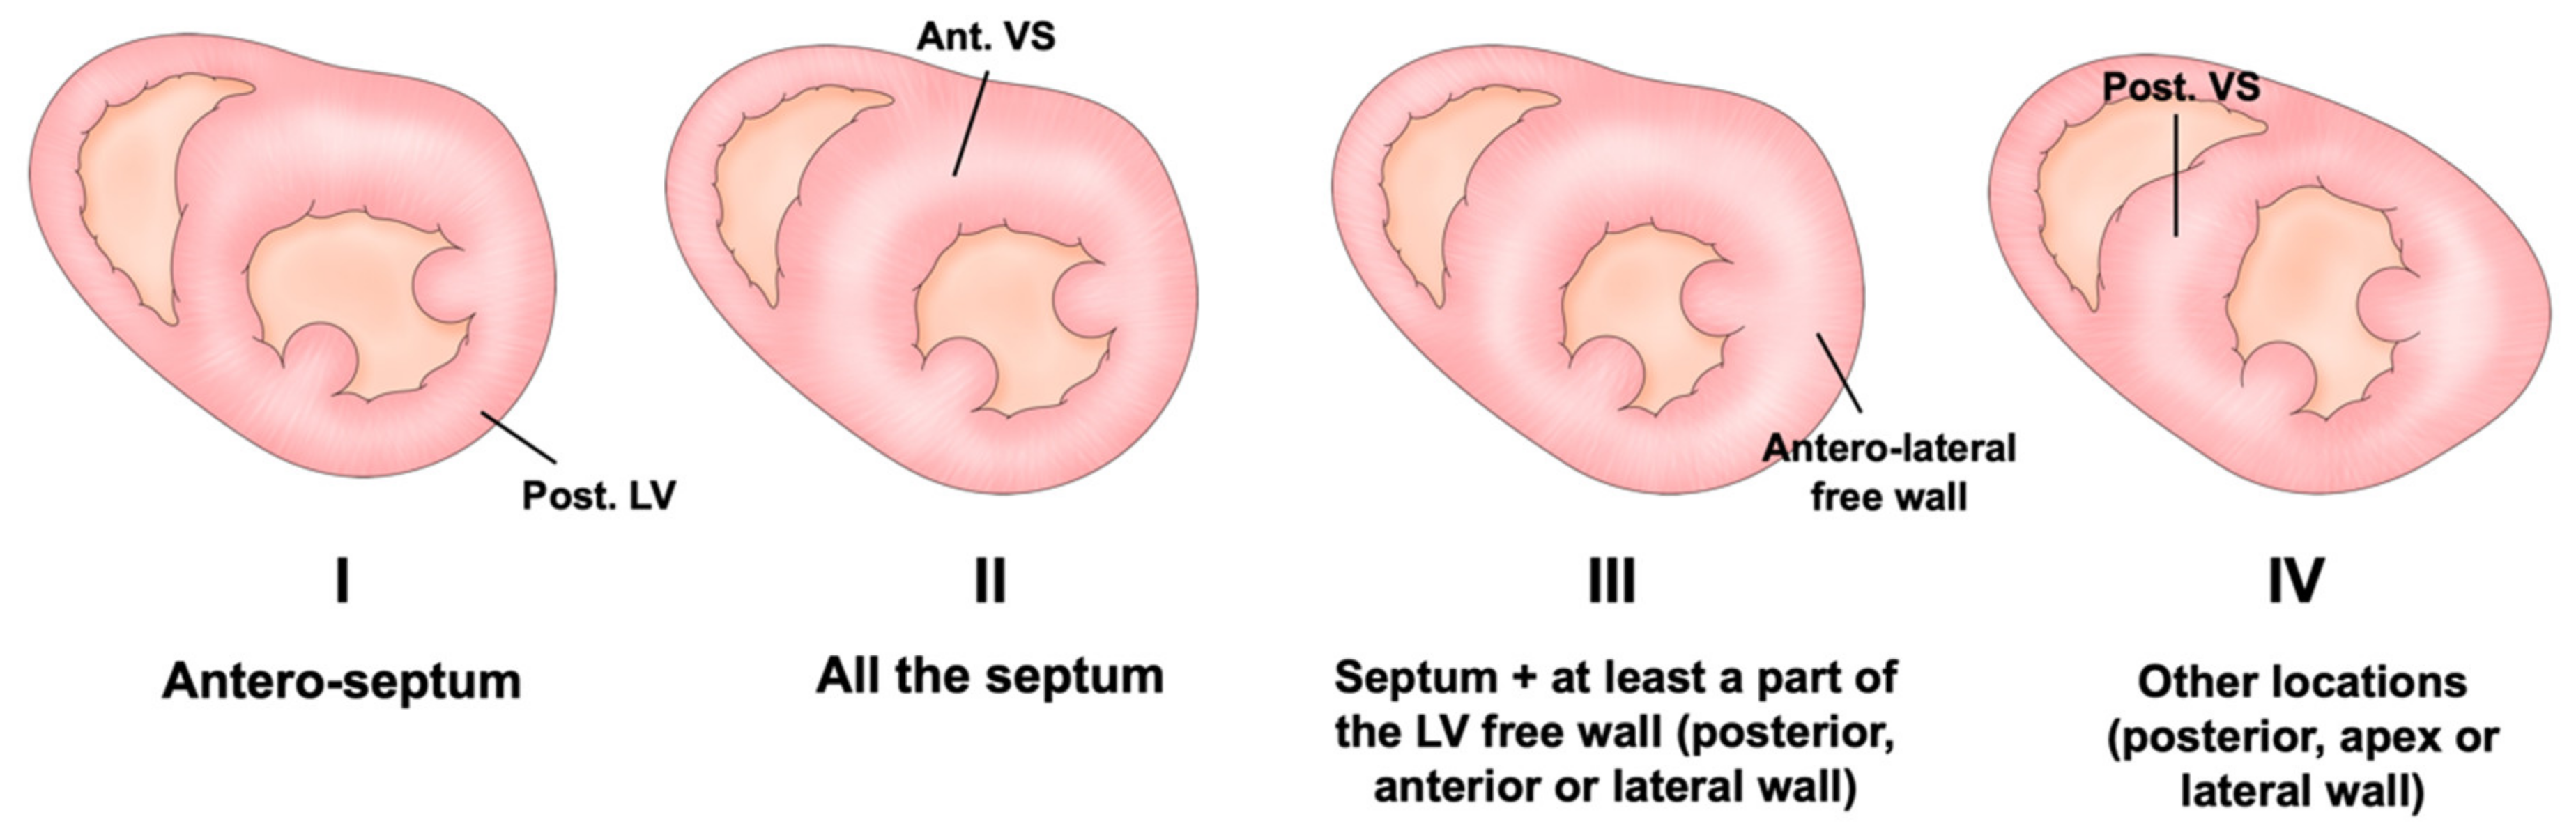

2. Diagnosis and Variation of Hypertrophy

Assessment of LV Wall Hypertrophy